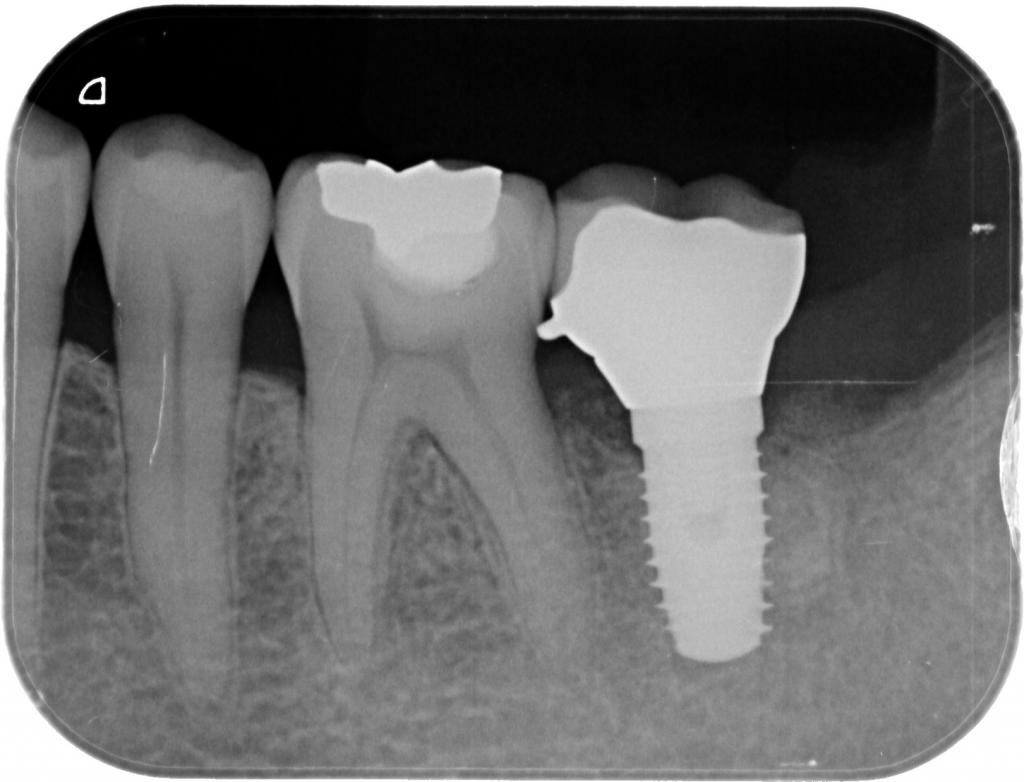

- 術後のレントゲン写真です。

インプラントの周りには充分な骨の造成が見られ、歯を無くした時とは別の状態になっています。